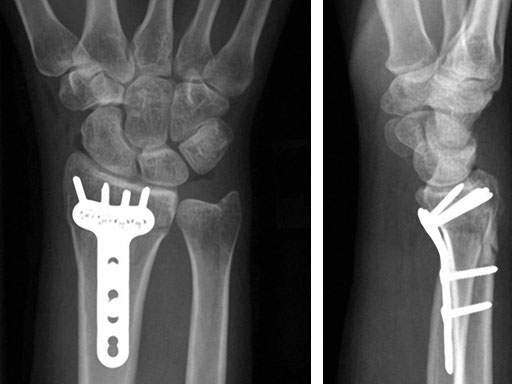

Fig 1ab Preoperative x-rays.

Fig 2ab X-rays postoperatively.